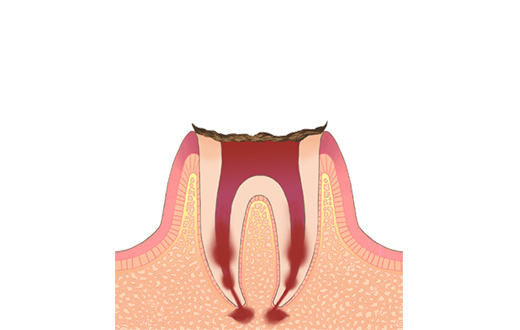

C4残根

虫歯によって、歯のほとんどが溶かされてしまった状態です。残しておくと、虫歯の巣になってしまうため、抜歯の必要があります。痛みがない場合がほとんどですが、痛みがないからと言って放置すると、ある日突然痛みだしたり、腫れたりすることがあります。